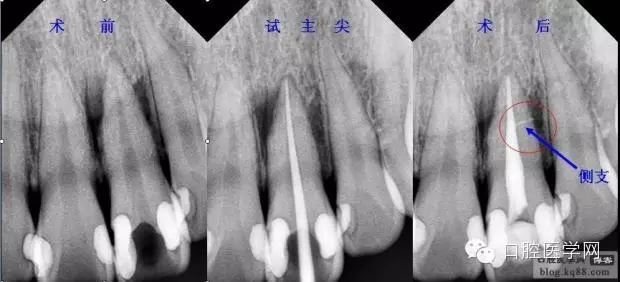

現(xiàn)代的根管充填技術(shù)是通過向預(yù)備好的根管充入牙膠和封閉劑達(dá)到高度的致密性、良好的錐度、精確的長度、所有根管空間(包括分支、側(cè)支、峽部、交通支)的完善封填。

首選錐度等于或稍小于主銼,粗細(xì)型號等同于主銼,比如主銼是8%25#,首選6%25#,如果粗了選擇6%20#,如果細(xì)了選擇6%30#。主尖合適后在尖端3mm要有牽拉感,而且施加合適的力量主尖也不會超出狹窄部。

主尖修切好后為了主尖斷面鋒利的邊緣變圓滑,也為了主尖的尖端更好的適應(yīng)根尖達(dá)到更好的封閉狹窄部,可以用修切后的主尖尖端在氯仿或熱水中蘸一下后快速插入工作長度讓軟化的尖端適合根管情況,相當(dāng)于定做的主尖,密封效果會更好。

試好后的主尖經(jīng)X片評價(jià)合適后要放入2.5%的次氯酸鈉中消毒備用,一般3分鐘就可以達(dá)到消毒標(biāo)準(zhǔn),然后充填時(shí)用氣槍吹干,不能用棉球或紗布擦。

五、根管濕潤下試主尖: